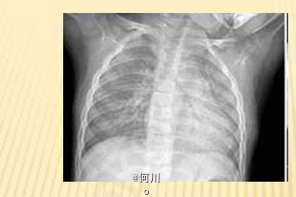

流涕、轻咳、低热、纳差 辅查胸片,X线表现为两肺纹理增粗、增多,模糊。CT可见双肺沿支气管分布的大片状模糊影